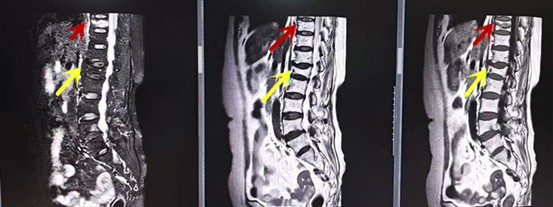

從左向右依次為CT矢狀位重建圖像、三維重建圖像、軸位掃描圖像,箭頭提示腰1椎體爆裂性骨折

紅色箭頭提示新鮮骨折,黃色箭頭提示陳舊性骨折